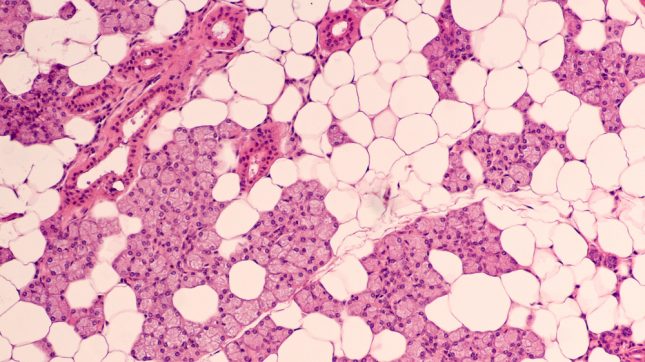

קרצינומה של צינורות הרוק

יש מחסור בראיות קליניות המדגימות את היעילות של טיפול סיסטמי עבור קרצינומה מתקדמת של דרכי הרוק (salivary duct carcinoma – SDC) לאור הנדירות של מחלה זו. החוקרים העריכו את היעילות והטוקסיות של טרסטוזומאב ודוקסטקסל במטופלים עם SDC מתקדמת מקומית, חוזרת או גרורתית חיובית לקולטן 2 ל-EGFR.